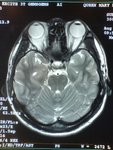

RadioEdric :: 我是白老鼠廿幾號 - 瑪麗醫院新裝之 3T 磁力共振掃瞄器